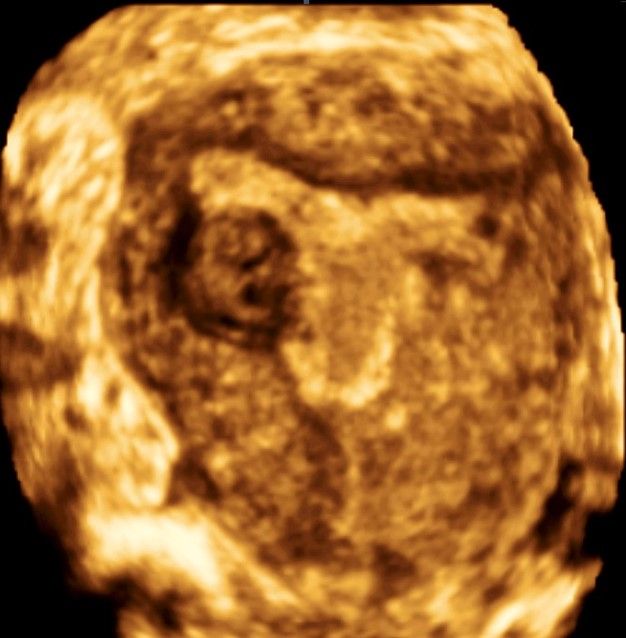

Современные экспертные УЗИ сканеры дают возможность проводить исследования всех органов в 3D. Это позволяет, используя полученный массив данных, получать диагностические сечения в любой плоскости, недоступной для обычного 2D УЗИ. Наиболее интересной является фронтальная. Например, визуализация полости матки. Диагностическая возможность выявления пороков развития превосходит все другие методы (рентгеновские и МРТ). Метод также позволяет уточнить положение ВМК (спирали) в полости матки, расположение миоматозных узлов, расположение плодного яйца на малых сроках, полипов. Сегодня современное экспертное ультразвуковое исследование невозможно без использования 3D УЗИ.